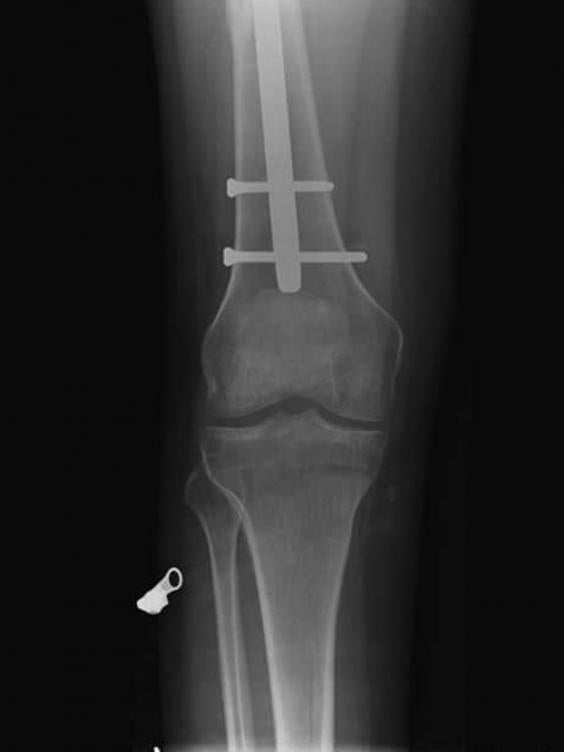

An X-ray showing the shattered bone of Carlo De Chiro (Carlo De Chiro/SWNS.com)

The accident put him in a wheelchair during his 18 months of recovery and he was left with a titanium rod in his leg permanently.

Carlo De Chiro's pinned and broken legs (Carlo De Chiro SWNS.com)